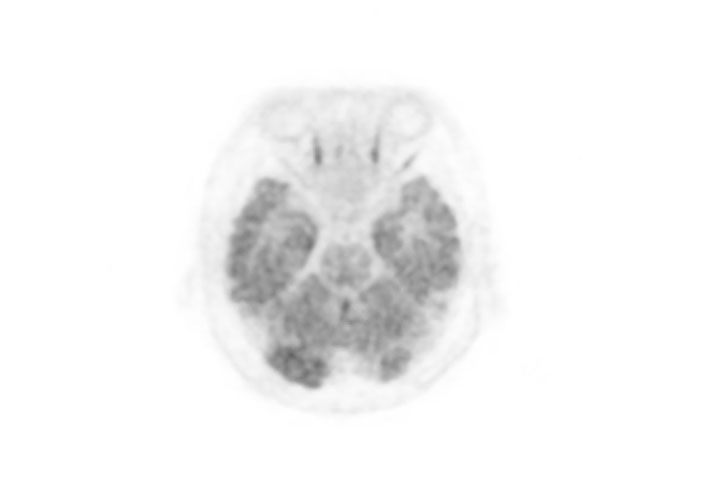

Head / Case3 : FDG

Axial

Courtesy : Kindai University Hospital

- Imaging protocol

- Injected dose: 4.49 MBq/kg, 18F-FDG

- Uptake time: 46 minutes

- Scan time: 30 minutes